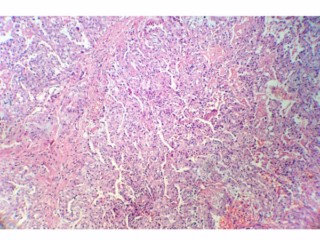

تشخیص:

عفونت قارچی

دکتر خدامی

فوق تخصص پاتولوژی